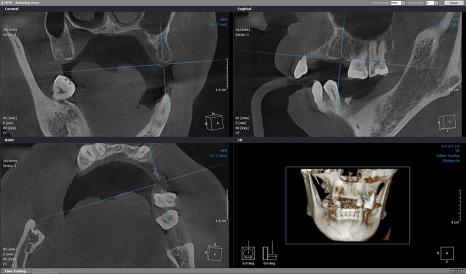

픽스처를 심은 후

골밀도가 부족한 부분은

이종골로 GBR을,

치근단 사진에서 좌측 상악

영구치(제 1대구치, 제 2대구치)가

손상된 곳은 신경 치료를 하기로 했습니다.

이어서 우측 임플란트를 위해

재검사를 시행했습니다.

처음과 같이 큰 변화는 없었지만

오차 없이 인공 치근을 식립하려면 검사는 필수죠 ^^